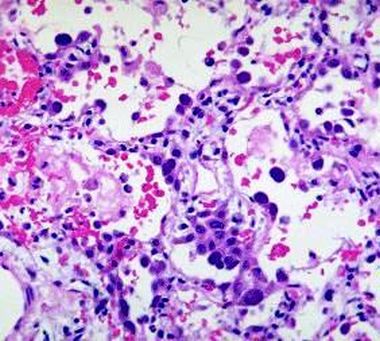

In uno studio, apparso di recente su Cell Reports, un team di ricercatori coordinati da Emilio Clementi e Clara De Palma del Dipartimento di Scienze biomediche e cliniche L. Sacco e dell’Asst Fatebenefratelli-Sacco, in collaborazione con l’Irccs E. Medea e Irccs Santa Lucia (Roma), ha identificato un collegamento tra la distrofia muscolare dei cingoli, nota come Limb Girdle Muscular Dystrophy (LGMD-2D), e un difetto nel processo di generazione dei mitocondri, associato ad un loro ridotto numero e ad una diminuita capacità ossidativa (energetica) del muscolo.